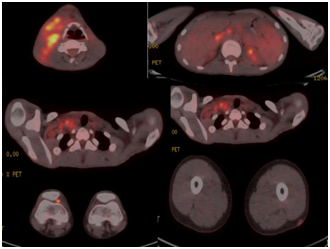

A 17-year-old male patient with a pre-diagnosed lymphoma who had hepatosplenomegaly on an abdominal US examination and lymphadenopathies thought to be compatible with malignancy with heterogeneous enhancement at the level of the right neck of the neck in the US and CT examinations were undergone PET-CT imaging. PET-CT images from the calvarium to the soles of the foot revealed conglomerated lymphadenopathies (SUVmax: 4.9-11.1) on the right dominant bilateral cervical chain extending to the right supra-infraclavicular area. In addition, bilateral paraaortic, paraceliac, aortocaval and peripancreatic lymphadenopathies with a maximal size of 1 cm (SUVmax: 8.2) and diffuse FDG activity (SUVmax: 2.7/2.0) relatively increased compared to liver parenchyma in the spleen and minimal diffuse FDG activity in the bone marrow were detected. The left femur proximal posterolateral diaphyseal area showed a subcutaneous nodular probable inflammatory nodal low level of metabolic activity and possible pathological lymphadenopathy at the level of the right knee (SUVmax: 6.7) (Figure 1). A biopsy was suggested to the patient. Right cervical excisional lymph node biopsy was performed, lymphoma was excluded and the patient was diagnosed with Kikuchi Fujimoto Disease. Appropriate treatment was started and a few months later PET-CT was negative for all regions.